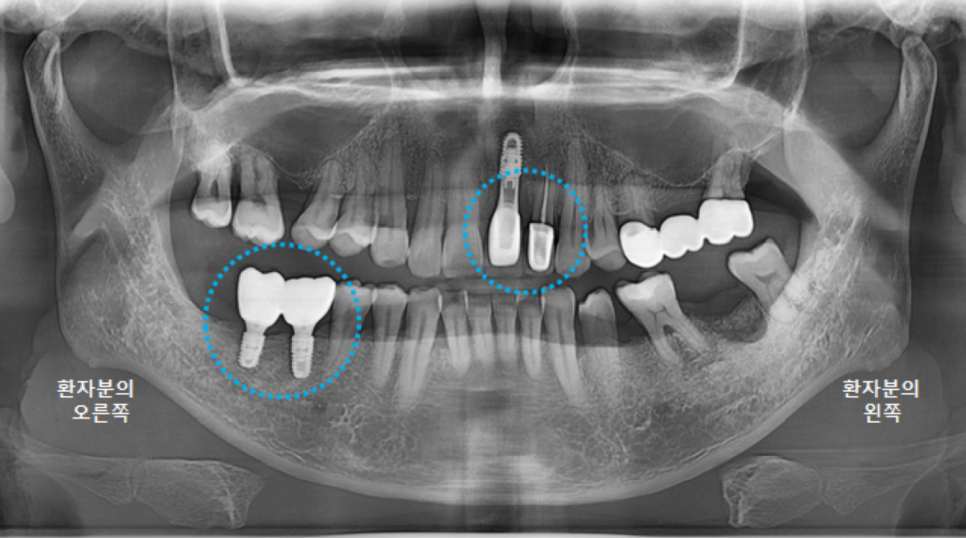

전체적인 구강 판단을 위해

파노라마 엑스레이 사진을 찍었습니다.

왼쪽 큰앞니도 빠져있지만,

오른쪽위 큰어금니, 오른쪽 아래 큰어금니도 발치된 상태였고,

왼쪽 위 브릿지 상태도 좋지는 않았습니다.

왼쪽 아래 큰어금니 하나는 뿌리만 남은 상태였어요.